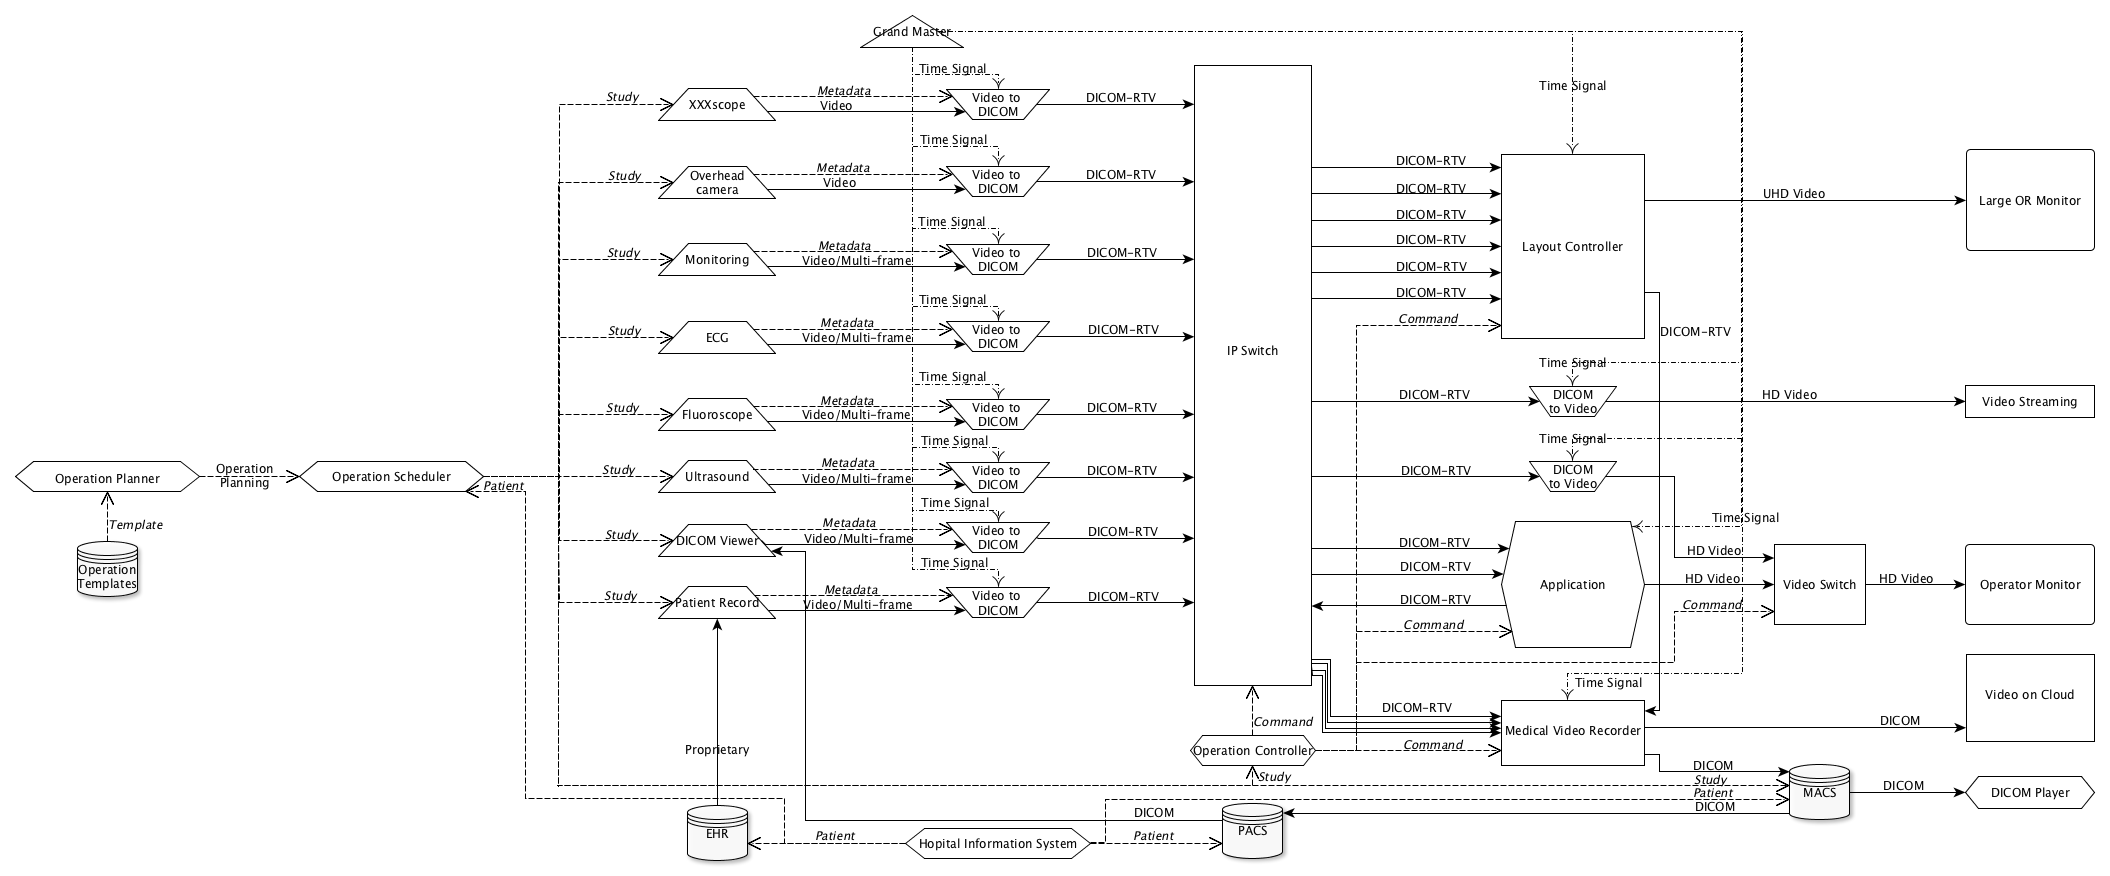

- PPPP. Real-Time Video Use Cases (Informative)

- PPPP.1. Introduction

- PPPP.2. Use Case: Duplicating Video On Additional Monitors

- PPPP.3. Use Case: Post Review by Senior

- PPPP.4. Use Case: Automatic Display in Operating Room (or)

- PPPP.5. Use Case: Augmented Reality

- PPPP.6. Use Case: Robotic Aided Surgery

- PPPP.7. Example of DICOM Real-Time Video Implementation

- PPPP.8. Storage Considerationa

- PPPP.9. Example of Engineering Implementation

- PPPP.20. Transmitting a Stereo Video

- PPPP.1-1. Overview diagram of operating room

- PPPP.1-2. Real-Time Video stream content overview

- PPPP.1-3. Real-Time Video transmission details

- PPPP.2-1. Duplicating on additional monitor

- PPPP.3-1. Recording multiple video sources

- PPPP.4-1. Displaying multiple source on one unique monitor

- PPPP.5-1. Application combining multiple real-time video sources

- PPPP.7-1. Example of implementation for Augmented reality based on optical image

- PPPP.7-2. Example of implementation for Augmented reality based on optical image

- PPPP.7-3. Example of implementation for Augmented reality based on digital image